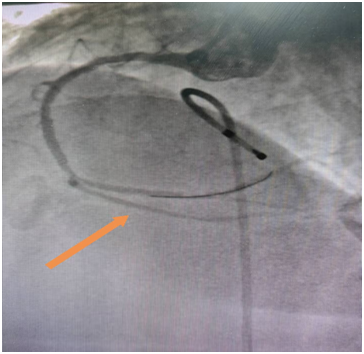

60岁的吴老伯患高血压病4年多,平时口服降压药物,没有规律监测血压,3年前患脑梗,治疗后好转,没有遗留明显后遗症,出院后没有规律服用药物治疗,出院时医师反复交代戒烟,吴老伯也没有放在心上。最近吴老伯在于熬夜后感头痛不适,起初头痛能自行缓解,随后感头痛症状反复发作,在快步行走及爬楼梯时明显,休息10多分钟可缓解,因症状反复发作,来到开阳县人民医院就诊,心血管内科医师在详细询问病史后,考虑吴老伯是冠心病高危人群,且头痛与活动相关,高度怀疑心绞痛,建议住院治疗,最开始吴老伯还很纳闷,明明是头痛来看病,怎么就变成心绞痛了?我没有胸痛啊!虽然心里有疑问,吴老伯还是接受医师的建议住院完善冠脉造影检查,果然冠脉造影明确了心脏回旋支有弥漫性狭窄,狭窄最重85%,前降支狭窄最重处75%,明确了头痛原因就是心绞痛。随即,心内科介入团队为吴老伯进行了回旋支支架植入术。植入支架后,吴老伯活动时头痛的症状也消失了。可以回家过个安稳的春节了。

冠脉造影结果

支架置入术后效果